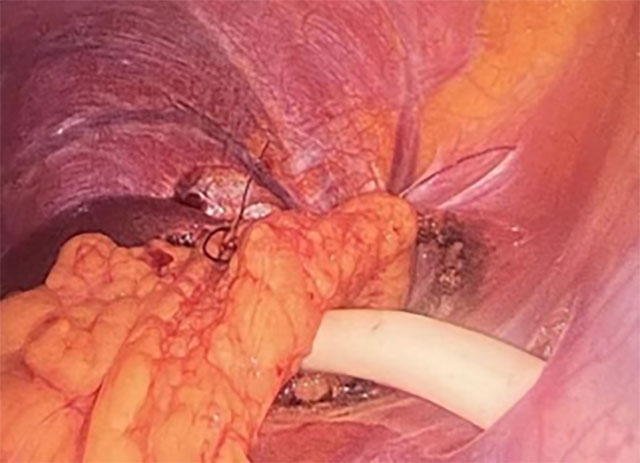

硬化剂囊肿硬化:先以硬化剂让囊肿壁失去分泌功能,从源头减少囊液;

腹腔镜开窗引流:再通过腹腔镜微创充分开窗,彻底排出囊液;

大网膜填塞死腔:随后用带蒂大网膜填塞囊腔死区,像加了层“防护垫”,防止膈肌与肝脏粘连;

镰状韧带固定引流:最后经镰状韧带置管持续引流,确保囊腔无积液愈合,既保留了腹腔镜微创、创伤小、恢复快的优势,又弥补了传统手术的不足。